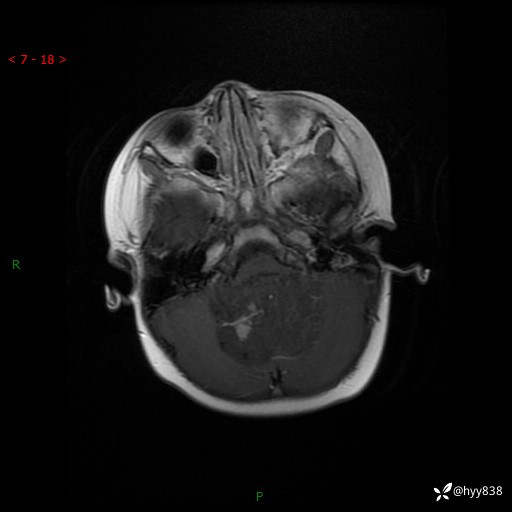

颅脑CT平扫

颅脑MRI平扫+增强

三脑室、四脑室多发病变,如何分析?